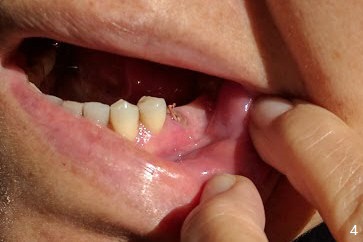

A 64-year-old woman has a lower left FPD (Fig.1) with the abutment at #20 having open margin (*). The tooth seems to be non-salvageable and to be replaced by an implant. There is ~ 6 mm native bone (Fig.2). Mesial osteotomy should be safer than orthodox one (Fig.3). To have the best reference, the FPD will be first sectioned between #19 and 20 (Fig.3 red line). Initial depth will be 18 mm (gingival level). An implant will be placed using the pontic at #19 and the tooth #21 for orientation guide. After placement of an abutment at #20 and use of gauze to seal the socket, the FPD will be sectioned between #18 and 19. It appears that the tooth #20 and probably #18 have fractured (Fig.4). Implants will be most likely placed at #18 and 20. The existing bridge will be used as a provisional.